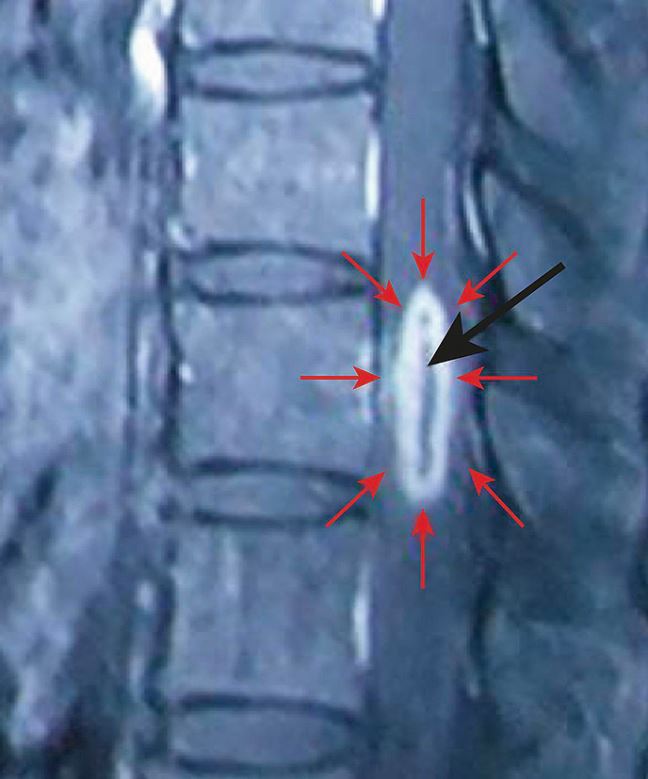

Ein junger Mann verspürte seit einem Monat eine progrediente Lähmung und Taubheit beider Beine. Bei der klinischen Untersuchung zeigte sich eine Hypästhesie vom 10. Brustwirbel aus abwärts. Die Laufmuskeln konnte der Patient nur noch zum Zucken bringen, wobei beide Beine eine Hyperreflexie zeigten.

Scharf begrenzte Läsion im Rückenmark.